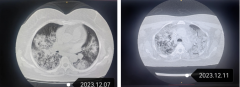

六旬阿姨发热、咳嗽、呼吸困难,一查是重症肺炎!东莞医院抢救

东莞的李阿姨今年61岁。12月6日,她晨起后出现发热、咳嗽、呼吸困难,被家属送到万江医院就诊。 急诊科接...